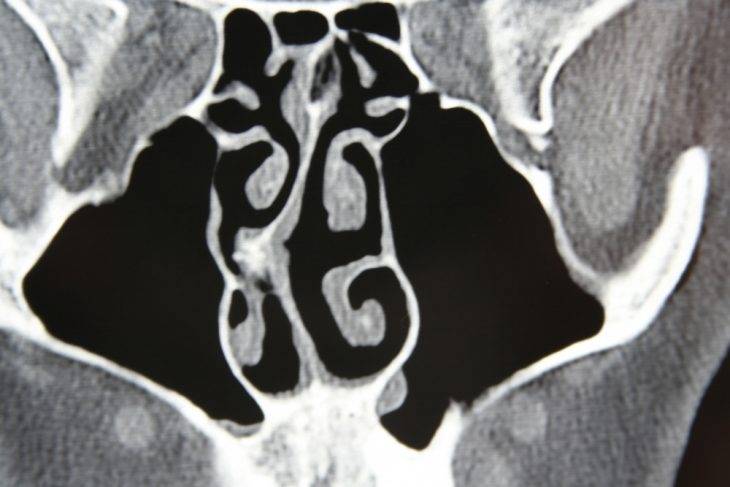

Искривление носовой перегородки на МРТ

Это относительно современный метод коррекции деформаций носовой перегородки, обладающий определенными ограничениями, но успешно применяемый в области оториноларингологии. Основой данного подхода является использование лазерного луча. Конкретные участки хрящевой части перегородки прогреваются до необходимой температуры и фиксируются в правильном положении с помощью тампонов на срок до суток. Процедура, проводимая под местной анестезией, занимает не более 15 минут. Лечение может осуществляться в амбулаторных условиях и практически не вызывает дискомфорта у пациента. Коррекция деформаций носовой перегородки с помощью лазера возможна только в тех случаях, когда искривлена исключительно хрящевая часть и не произошло ее повреждение.